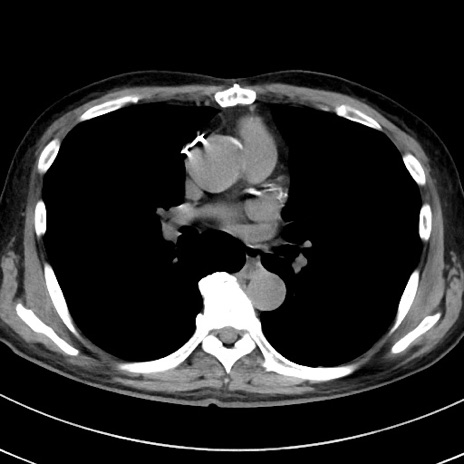

症例

冠状断像